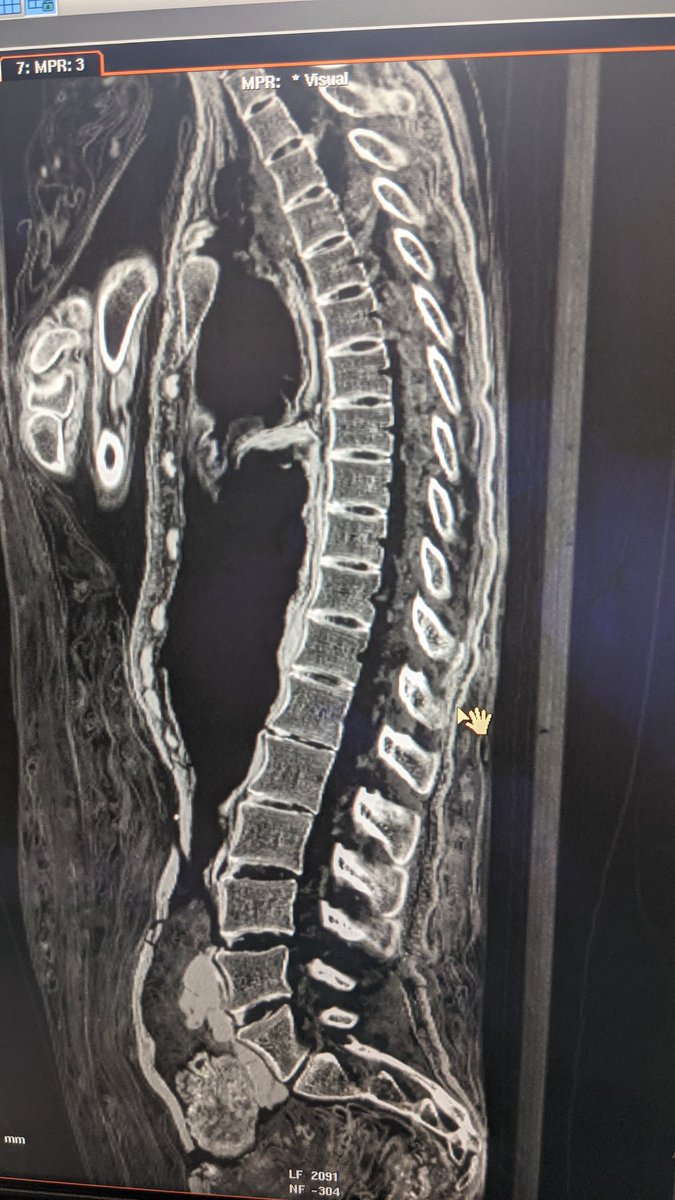

Une colonne vertébrale en bon état chez cette momie qui était a priori une femme jeune Image